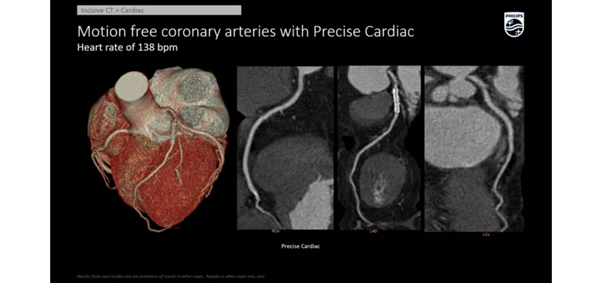

- 128 срезов и выше: экспертный класс для кардиологии, например коронарографии или перфузии.

Скорость вращения

- 0,35–0,4 секунды — оптимальна для исследования легких и сосудов.

- Менее 0,3 секунды — важна для кардиологии и педиатрии, так как дети часто не могут лежать неподвижно.